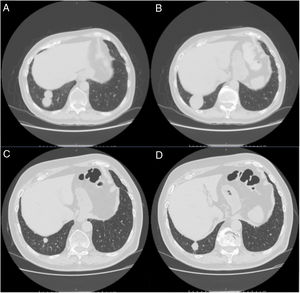

A 79-year-old man, a non-smoker and who had a history of atrial fibrillation, was treated with amiodarone 400mg daily for 3 years. During the last 2 months of treatment, he was presented with exertional dyspnea and dry cough. Respiratory function tests revealed a restrictive ventilatory pattern with a moderate reduction in carbon dioxide lung diffusion (DLCO) (14.3mL/min/mmHg, 55% of predicted value). Chest computed tomography (CT) showed bilateral, peripheral, predominantly basal ground-glass and reticular opacities consistent with a NSIP radiological pattern (Fig. 1, panels A and B). The bronchoalveolar lavage showed a significant amount of foamy macrophages. Transbronchial lung biopsy of the right lower lobe was performed and the histological examination revealed the presence of septal widening with type II pneumocytes hyperplasia, areas of organized interstitial fibrosis with sporadic fibrinous exudates, fibroblasts and collagen deposition next to aggregates of inflammatory cells and considerable amount of foamy histiocytes. These findings were consistent with a diagnosis of APT (Fig. 1, panels C and D). Other etiologies of interstitial lung disease (ILD) were carefully ruled out. Amiodarone was suspended while prednisone 40mg daily and oral anticoagulants were given, with rapid clinical and functional recovery. At 40 days, ground-glass and reticular opacities had almost completely resolved on CT scan while two soft-tissue nodules of 25 and 11mm, respectively, were identified in the right costophrenic sulcus (Fig. 2, panels A and B). Both lesions presented elevated density on CT scan images with Hounsfield Unit (HU) values ranging from 46 to 50. The patient underwent a new bronchoscopy with bronchoalveolar lavage of the right lower lobe, but microbiological and cytological investigations were unremarkable. A tuberculin skin test and blood serological markers for autoimmunity, inflammatory and infectious disease were also performed with negative results. Moreover a supplemental investigation was conducted excluding the onset of new drug treatment, trauma or exposure to environmental agents. Given their rapid onset, the elevated HU values and the exclusion of other coherent etiologies, the nodules were interpreted as an unusual subacute manifestation of APT. As physical insult to pulmonary parenchyma is known to increase susceptibility to toxicity even if low dose amiodarone treatment is used,1 surgical lung biopsy was not performed and radiological follow-up was started. At 18 months, follow-up CT showed a considerable reduction in the size of both lung nodules (Fig. 2, panels C and D) and the clinical condition of the patient was unremarkable.

(Panels A and B) CT scan images showing predominantly basal, bilateral, peripheral ground-glass opacities with associated reticular abnormalities consistent with a non-specific interstitial pneumonia (NSIP) radiological pattern. (Panels C and D) Histological appearance at different magnifications of transbronchial biopsies showing areas of organized fibrosis with fibrinous exudates and significant amount of inflammatory cells and with no evidence of malignant cells.